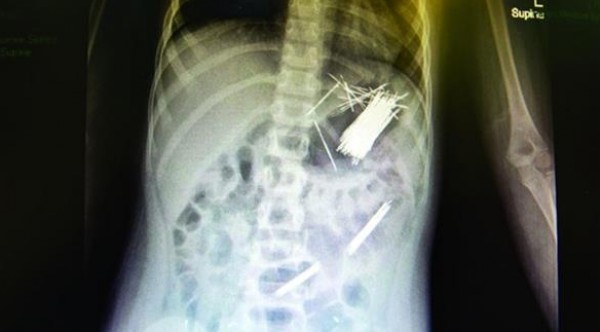

تمكن فريق طبي في أحد المستشفيات بمدينة أبها السعودية من استخراج 50 دبوساً للشعر من معدة طفل عمره سبع سنوات، عن طريق جراحة المنظار، وفقاً لصحيفة الرياض اليوم الأربعاء.

قال مدير مستشفى أبها للولادة والأطفال الدكتور علي بن مستور القحطاني إن العملية استغرقت ثلاث ساعات، ونقل المريض لجناح التنويم بعد إجراء العملية بدون أي مضاعفات.